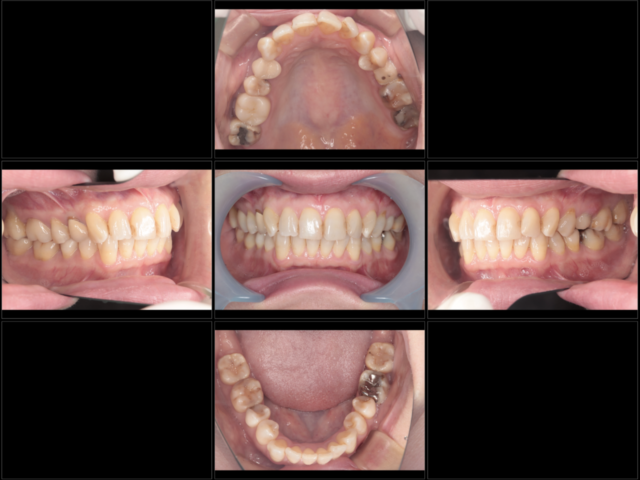

初診時

-

終了時